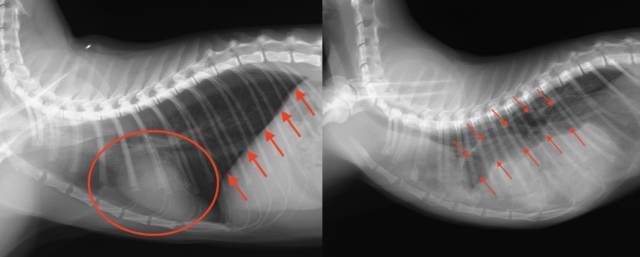

正常なレントゲン(左)では、横隔膜(赤矢印)と心臓(赤丸)がはっきり見えますが、横隔膜ヘルニアのレントゲン(右)では、横隔膜と心臓が見えず、胸の中に腸(赤矢印)が入り込んでいます